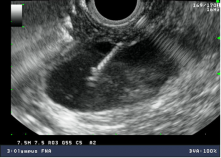

A Ecoendoscopia Digestiva, ou ultra-sonografia endoscópica (USE), é um exame que combina endoscopia e ecografia de alta resolução. O aparelho utilizado para a realização do exame designa-se ecoendoscópio. Trata-se de um endoscópio fino e flexível, especialmente equipado com uma sonda (transdutor) de ecografia em miniatura que se encontra acoplada à extremidade do aparelho, e que permite a realização de ecografia no interior do tubo digestivo.

O ecoendoscópio combina duas modalidades que, em simultâneo, integram a visão endoscópica e a ultra-sonografia de alta frequência.

O ecoendoscópio pode ser introduzido através da boca (Ecoendoscopia Digestiva Alta, para avaliação do esófago, estômago e duodeno) ou do ânus (Ecoendoscopia Digestiva Baixa, para avaliação do cólon e reto). O transdutor ecográfico permite obter imagens detalhadas das diversas camadas da parede do tubo digestivo em toda a sua espessura, bem como avaliar em profundidade outras estruturas vizinhas do aparelho digestivo, incluindo gânglios linfáticos, vasos sanguíneos e, no caso da Ecoendoscopia Digestiva Alta, o mediastino, pulmões, fígado, vesícula biliar, vias biliares e pâncreas, glândula suprarrenal, rim, ou seja, qualquer órgão ou estrutura próximo ao aparelho digestivo.

Enquanto a endoscopia clássica apenas permite observar a mucosa (camada mais interna do aparelho digestivo), a ecoendoscopia permite, através do transdutor ecográfico posicionado no interior da lúz do órgão, avaliar todas as camadas da parede do tubo digestivo e eventual patologia aí existente.